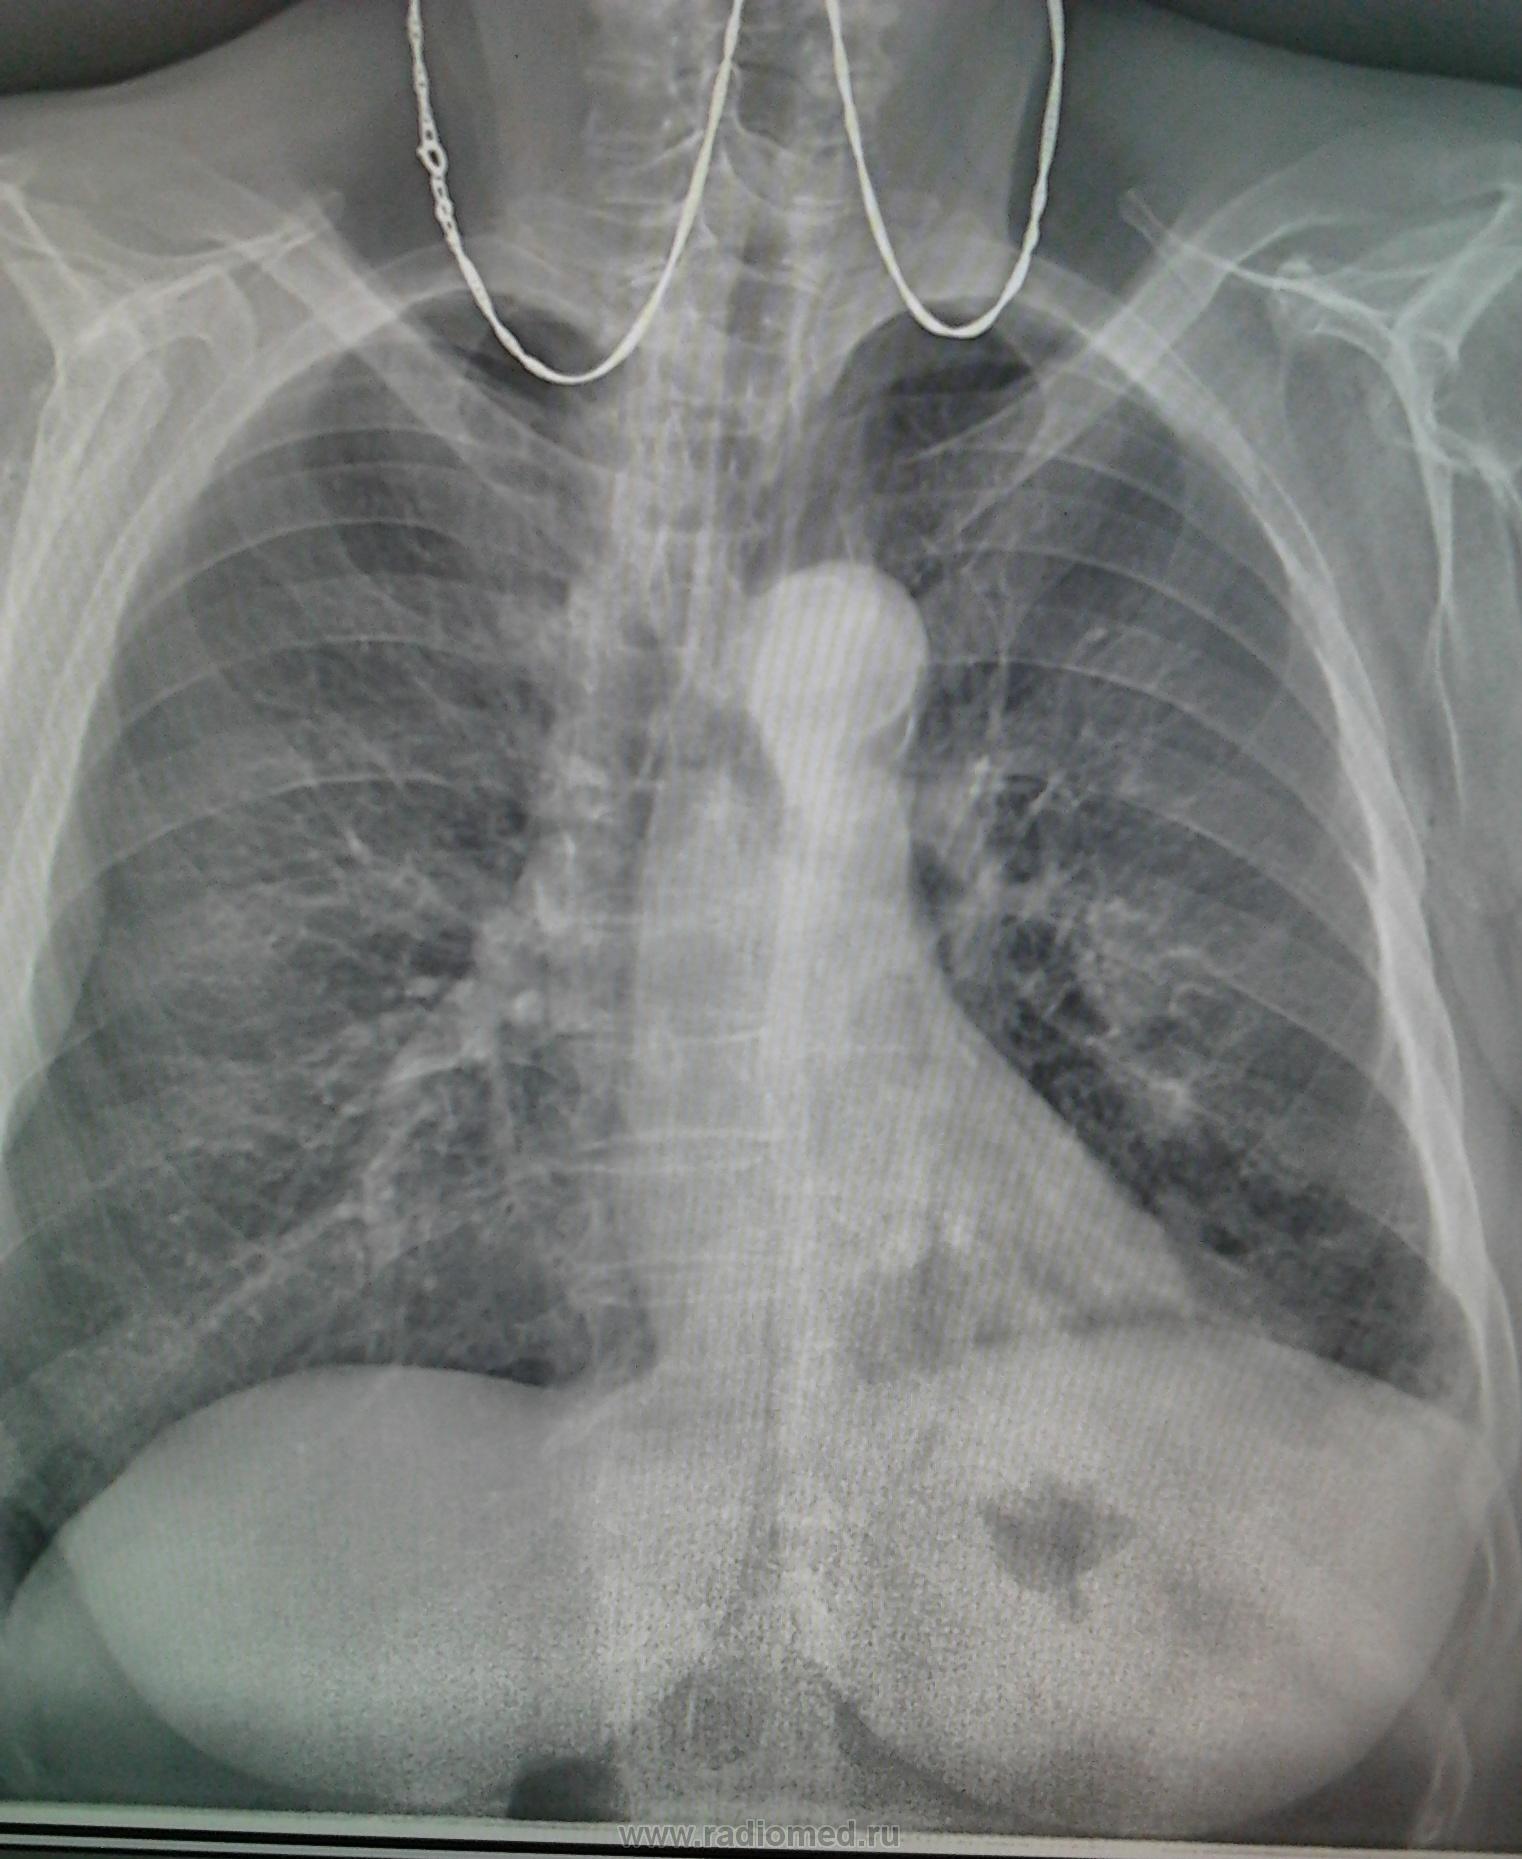

Снимок легких при туберкулезе является важным методом диагностики этого заболевания. На рентгеновских снимках можно увидеть изменения в легких, которые свойственны туберкулезу.

Рентген грудной клетки туберкулез

Рентген грудной клетки туберкулез

Рентгенография грудной клетки туберкулез

Рентгенография грудной клетки туберкулез

Рентген грудной клетки туберкулез

Рентген грудной клетки туберкулез

Фотографии снимков легких при туберкулезе

В данной статье представлены многочисленные фотографии снимков легких при туберкулезе, чтобы помочь вам понять, как выглядят изменения легких на рентгеновских снимках при этом заболевании.